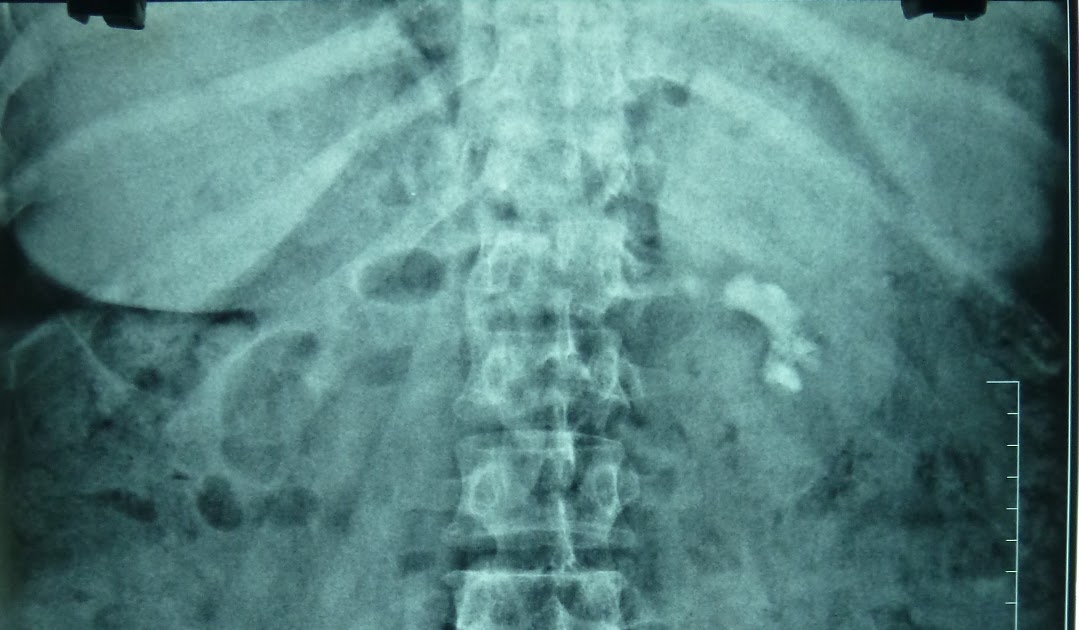

From drramayyas.blogspot.com

Ramayya Pramila Urology Hospital Partial staghorn kidney stone removed What Is A Partial Kidney Removal Called a partial kidney removal is a treatment option for some kidney tumors. a nephrectomy is the surgical removal of one kidney. It allows you to retain some kidney function. The goal is to remove the diseased or. It is recommended whenever possible. a partial nephrectomy is a surgical procedure to remove a portion of your kidney while. What Is A Partial Kidney Removal Called.